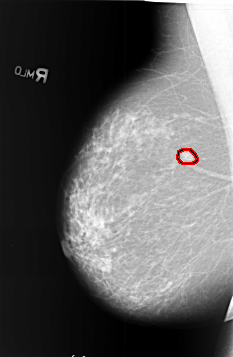

FILE: B_3405_1.RIGHT_MLO.OVERLAY

TOTAL_ABNORMALITIES 1

ABNORMALITY 1

LESION_TYPE MASS SHAPE OVAL MARGINS SPICULATED

ASSESSMENT 5

SUBTLETY 4

PATHOLOGY MALIGNANT

TOTAL_OUTLINES 1

BOUNDARY